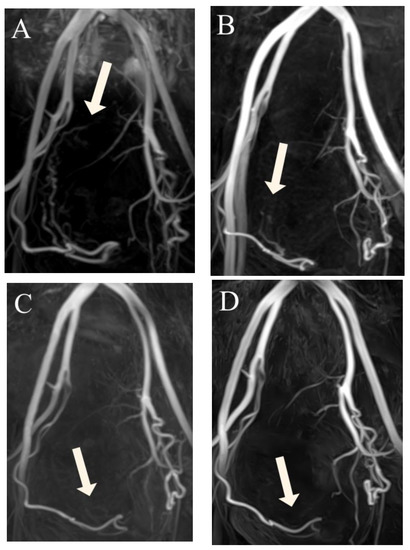

Figure 3.

(A–D) Three-dimensional non-contrast-enhanced magnetic resonance angiography image from a 49-year-old woman, suggesting luminal recanalization of the uterine arteries after uterine artery embolization. (A) Before uterine artery embolization: visualization of the right UA (arrow) forming the peritumoral plexus (score 4). (B) Three months after uterine artery embolization: visualization of the right uterine artery (arrow) until the ascending segment (score 3). (C) Six months after uterine artery embolization: visualization of right uterine artery (arrow) until the transverse segment (score 2). (D) Twelve months after uterine artery embolization: visualization of the right uterine artery (arrow) until the ascending segment (score 3).